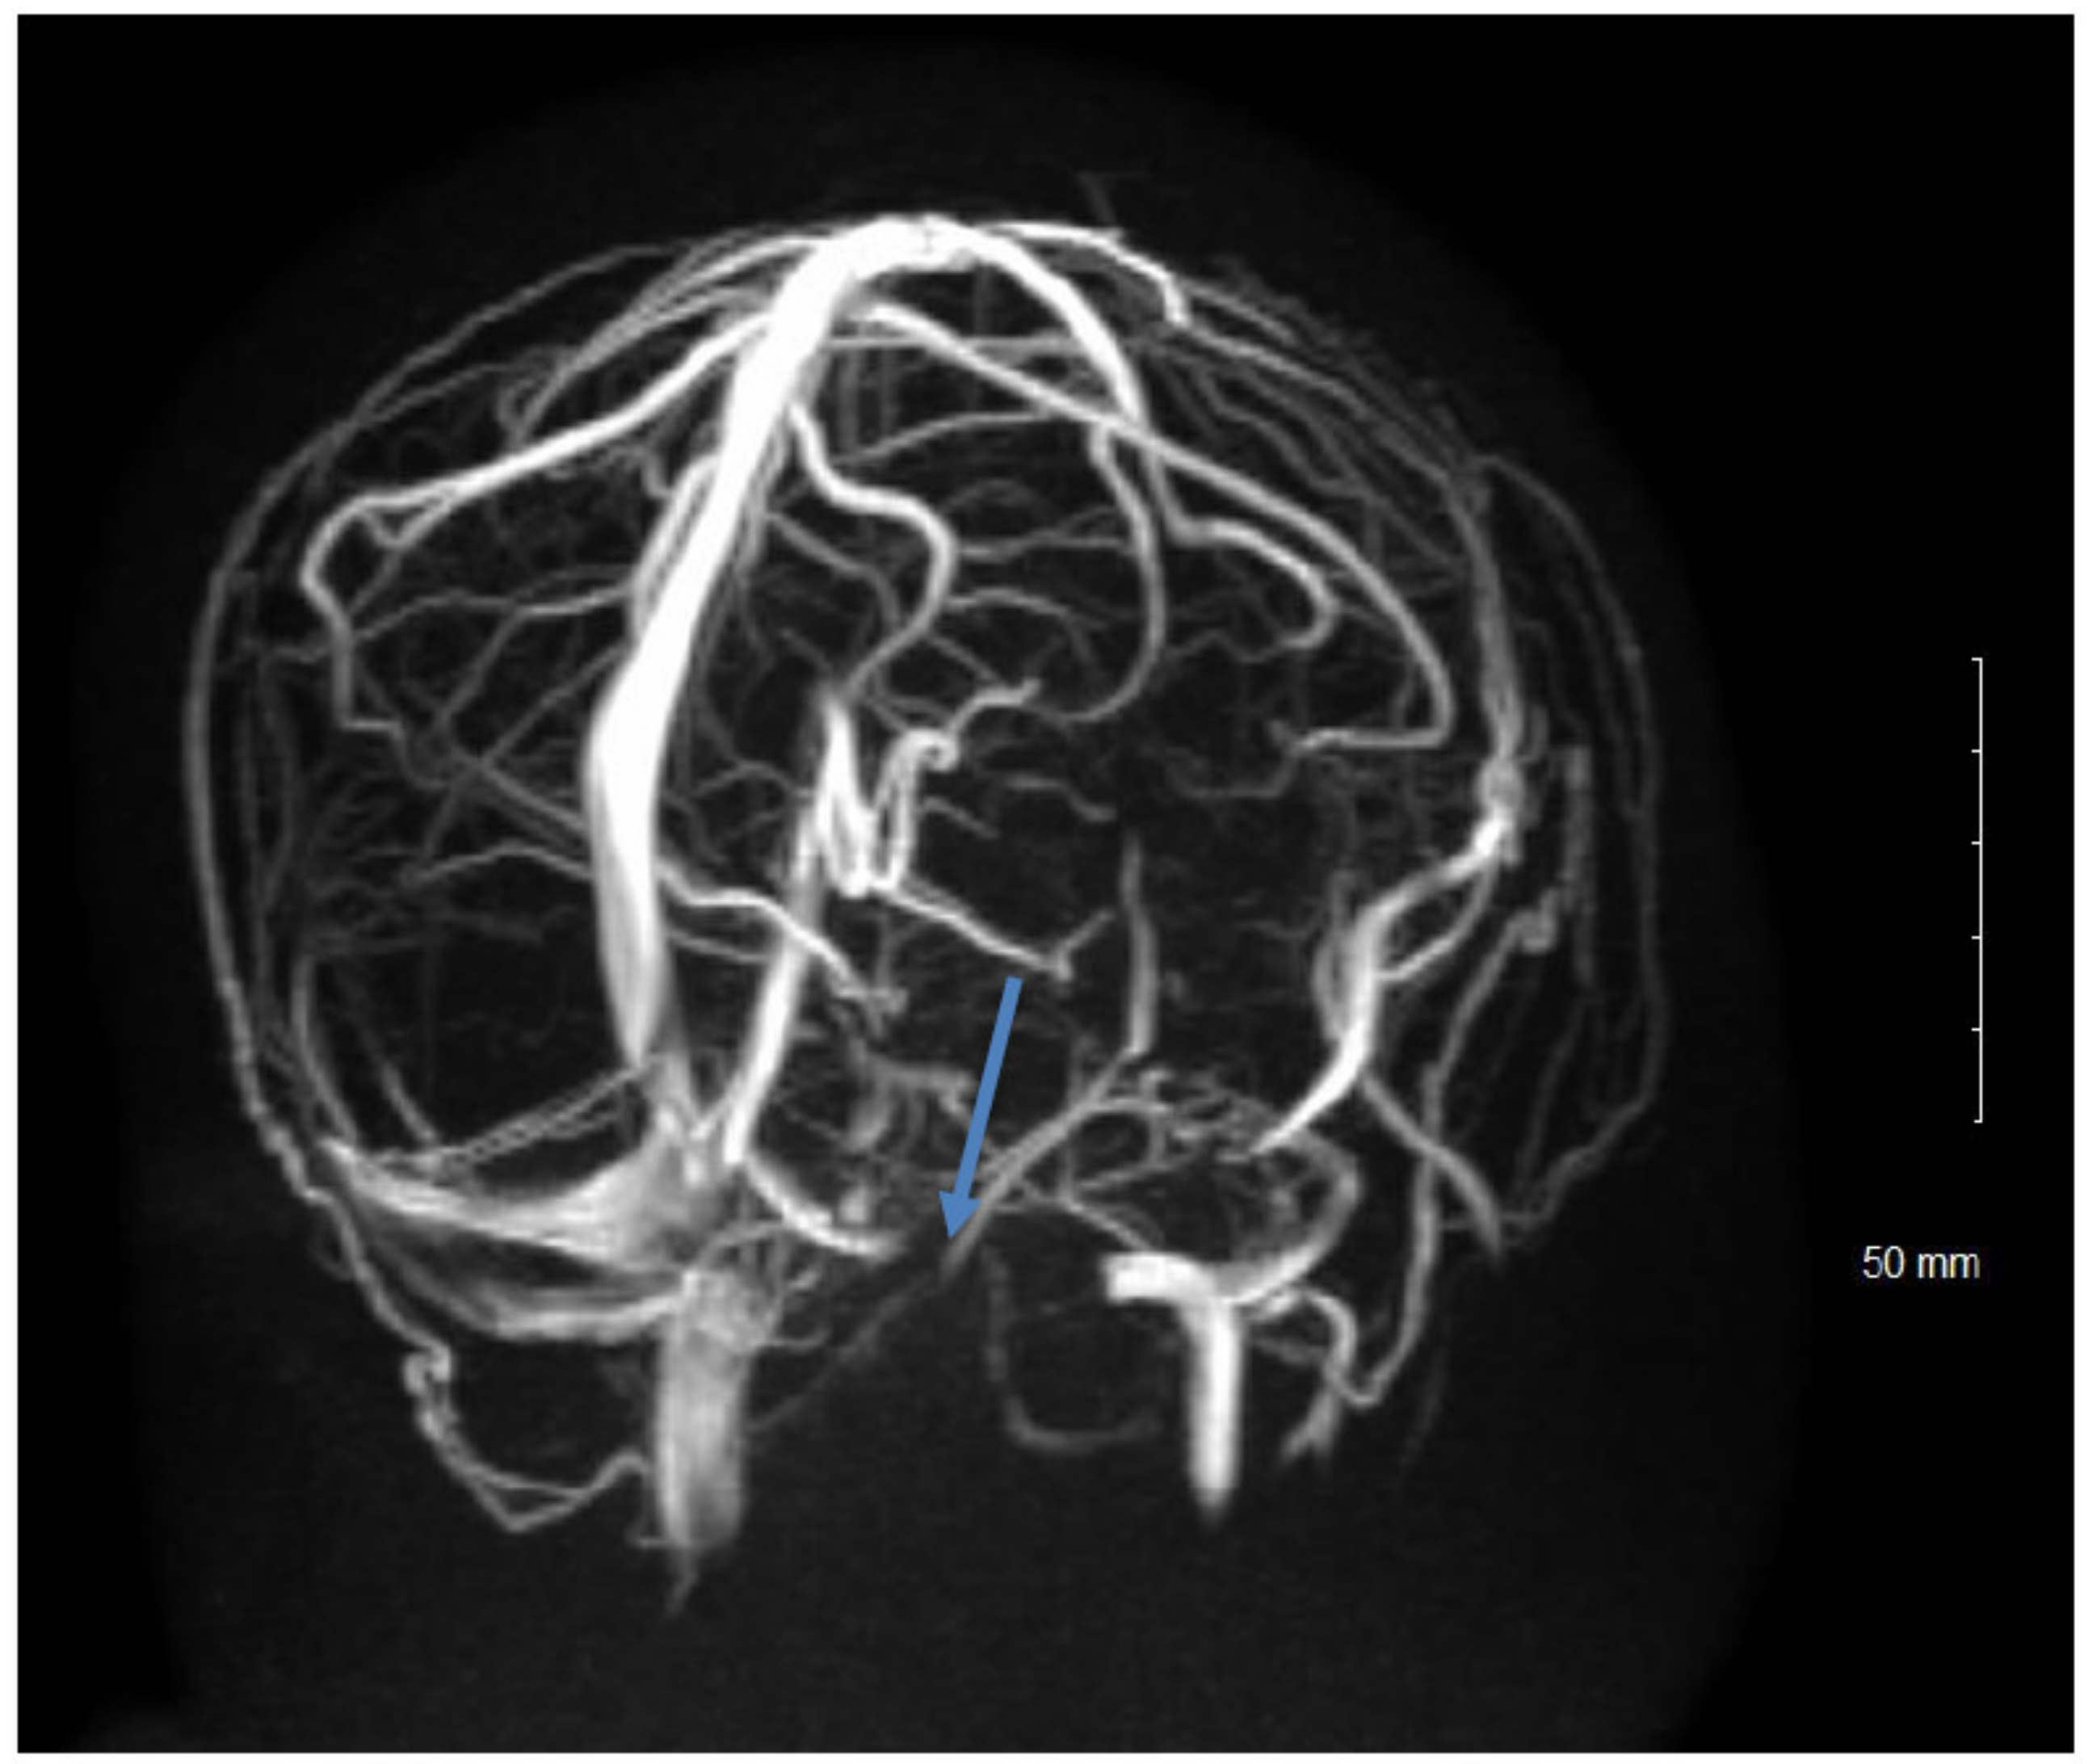

Examination and Investigations